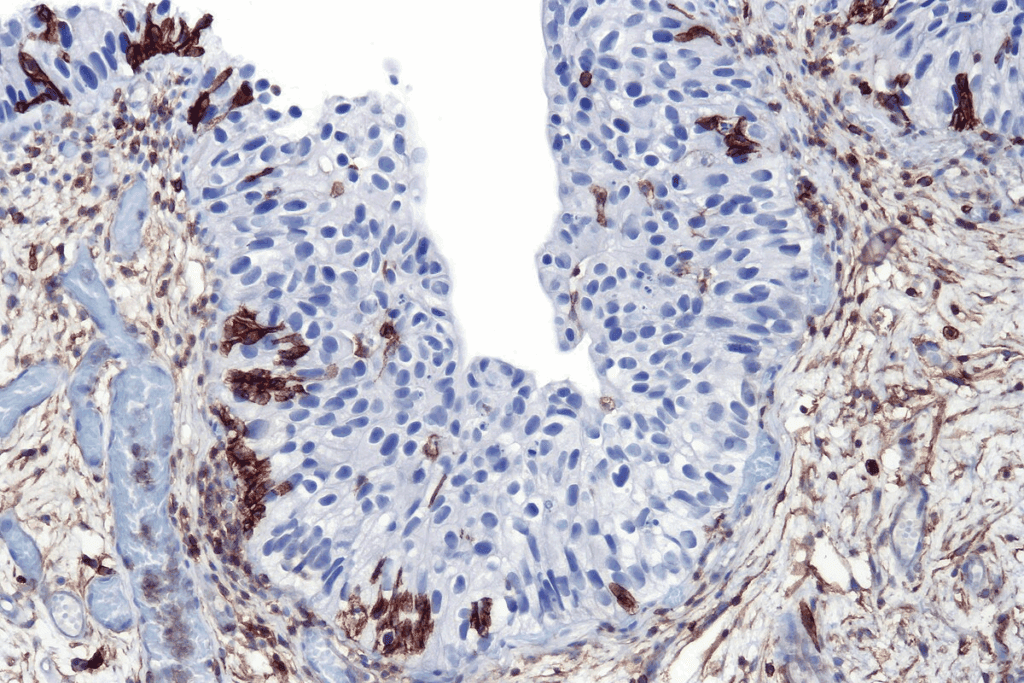

Microscopic Appearance

Under a microscope, CIS cells show distinct features. Their structure is disorganized, unlike normal cells. This disorganization is a sign of abnormal growth in CIS.

| CIS Cells | Disorganized | Present | No Stromal Invasion |

CIS is classified as stage 0 cancer (TisN0M0). Knowing about CIS’s biology is key for early detection and treatment.